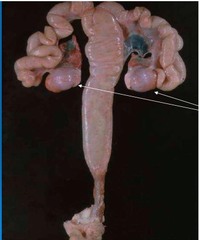

pyometra liquefactive necrosis (suppurative) purulent exudate

Front

disease type of necrosis type of exudate

Back

Small intestine: severe, subactue, multifocal, surface, Pyogranulomatous vasculitis, .

Morphological diagnosis